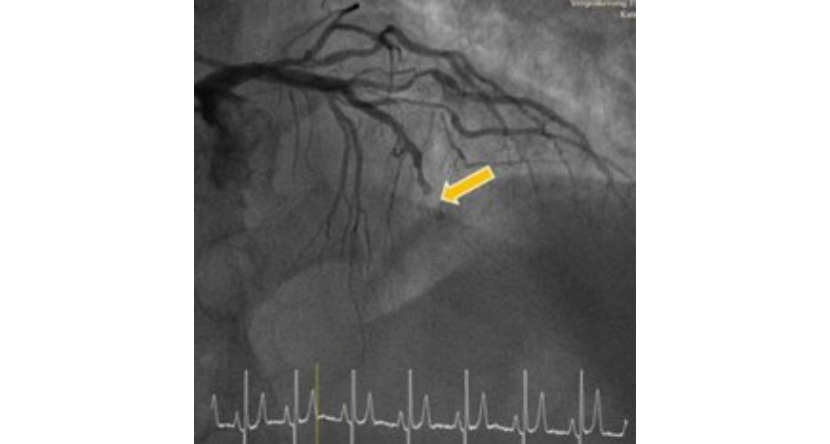

Balon dilatasyonu ve stent implantasyonu

En etkili yöntem, tıkalı koroner arterin balon dilatasyonu ve stent implantasyonu ile koroner anjiyografidir.Acil kalp kateterizasyonu (koroner anjiyografi) sırasında, tıkalı koroner arter ince bir tel ile incelenir ve ardından balon dilatasyonu ve stent implantasyonu ile tekrar açılır. Bu, kalp kasının etkilenen bölgesine kan akışını geri kazandırır ve iyileşme sürecini başlatır.